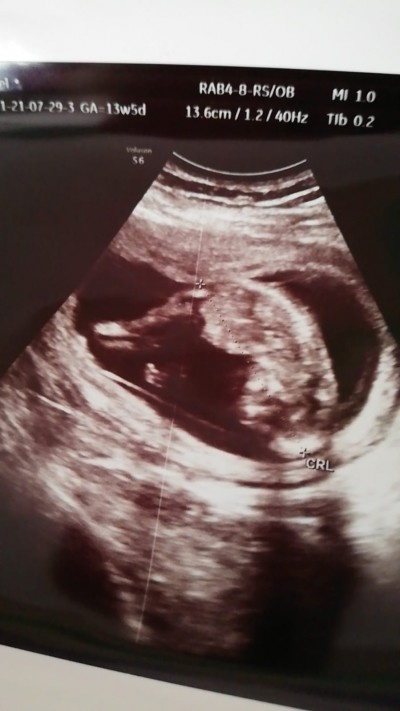

Cinsiyeti nedir sizce anlayan bakabilir mi?

13 haftalık canim

Kız çocuk amuda kalkmış :D erkek gibi duruyor canim

Bana erkeği anımsattı ama doktor bilir tabiki 13 haftalikmissin zaten bı kaç haftaya net öğrenirsin

Kız bacak arası boş geldi  bana